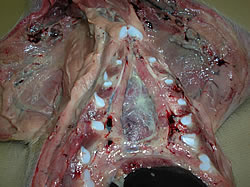

As lesões observadas na necropsia mostram presença de poliserosite (pericardite fibrinosa, pleuresia e peritonite fibrinosa, artrite).

|

|

|

Poliserosite

|

Pericardite

|

|

|

|

Peritonite

|

Artrite